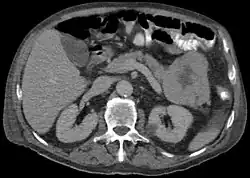

Acinar cell carcinoma of the pancreas

Acinar cell carcinoma of the pancreas, also acinar cell carcinoma, is a rare malignant exocrine tumour of the pancreas. It represents 5% of all exocrine tumours of the pancreas, making it the second most common type of pancreatic cancer.[1] It is abbreviated ACC. It typically has a guarded prognosis.

ACC are typically large, up to 10 cm, and soft compared to pancreatic adenocarcinoma, lacking its dense stroma. They can arise in any part of the pancreas.[2]

Histomorphologically, the tumour resembles the cells of the pancreatic acini and, typically, have moderate granular cytoplasm that stain with both PAS and PASD.[4]